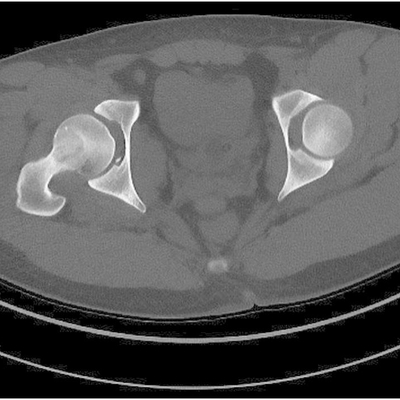

Click on an image below to view more info.